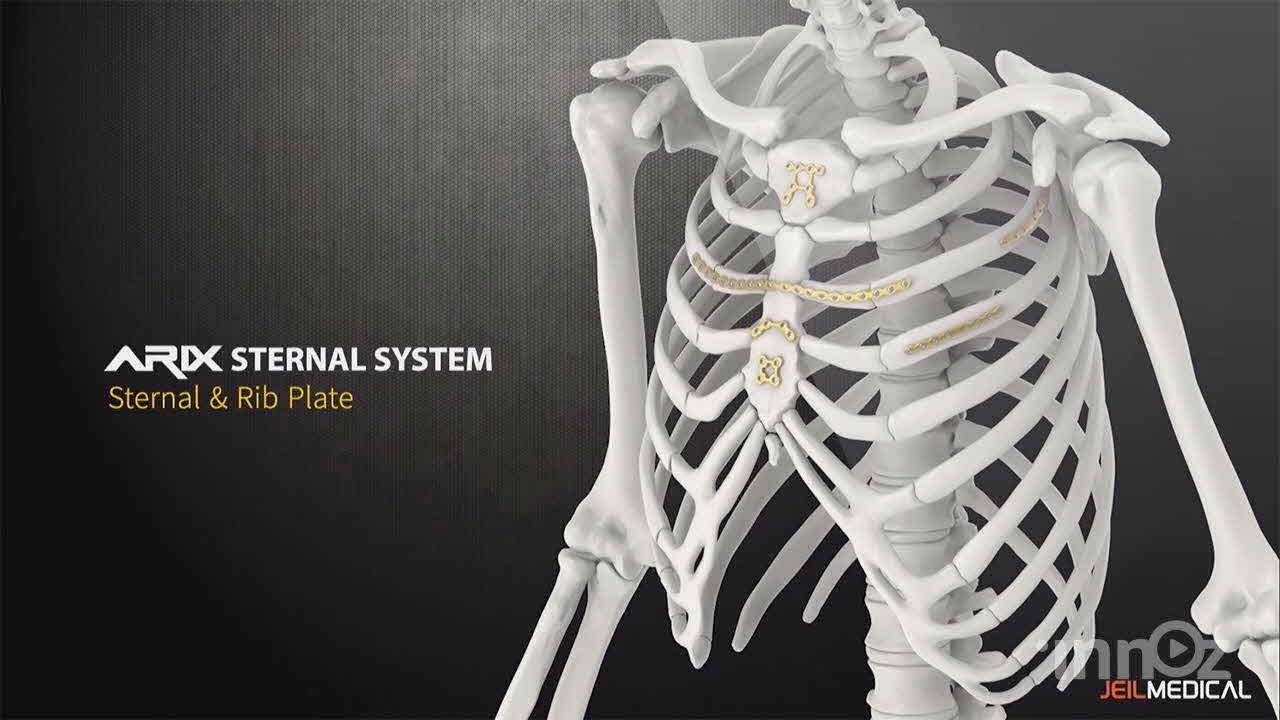

제일메디칼

제일메디칼

제일메디칼

제일메디칼

제일메디칼